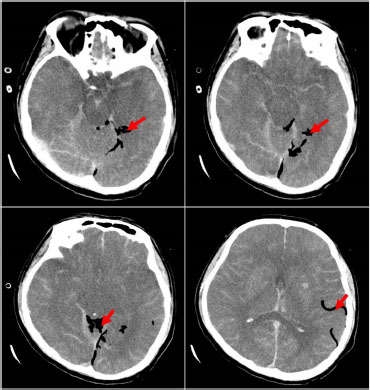

A 41-year-old male was admitted to the intensive care unit with sustained chills and fevers for 1 week and coma for 5 h. Leukocyte, neutrophil, C-reactive protein, and procalcitonin levels were high and platelet level was low. There was a significant increase in glycosylated hemoglobin, indicating undiagnosed diabetes mellitus or poor glucose control. Computed tomography (CT) revealed liver abscess with a large fluid–gas plane, but indicated no brain abnormalities (Figure 1). A diagnosis of GFPLA was made; percutaneous abscess drainage combined with anti-infective therapy was carried out, but the patient’s condition deteriorated, and bilateral pupil dilatation occurred on the next day. Immediate CT review showed brain edema and subarachnoid hemorrhage despite decrease in hepatic fluid and gas levels (Figure 2). A culture of abscess fluid and blood, along with next-generation sequencing yielded a definitive diagnosis of K. pneumoniae infection (Figures 3). Anaerobic and fungal cultures were negative. Anti-infective therapy based on drug-sensitive experiments was administered (imipenem cilastatin 2 g, every 6 hours), but the treatment was not effective and the patient eventually died of progressive cerebral swelling, herniation, and pneuomocrania (Figure 4).

GFPLA is mainly diagnosed via ultrasound (US) or a computerized tomography (CT) scan. Lee et al.[3] reported 100% detection rate through either US or CT. Relevant studies have shown that monomicrobial K. pneumoniae was the most common bacterium found in patients with GFPLA.[3,6] K. pneumoniae was found in 85.9% (80.6%–100%) of positive liver pus cultures in GFPLA patients versus 67.7% (65.8%–85.7%) in non-GFPLA patients. In this case, the pus cavity and blood culture of the patient were confirmed to be K. pneumoniae, but the cerebrospinal fluid culture could not be performed due to the existence of cerebral hernia. Therefore, the intracranial metastasis of K. pneumoniae could not be directly confirmed. However, recent studies have indicated that K. pneumoniae-induced GFPLA is significantly associated with metabolic disorders including hypertension, diabetes, and fatty liver. Poorly controlled diabetes is probably an independent risk factor for extrahepatic complications.[7] Glucose fermentation by bacteria causes the accumulation of formic acid, which is metabolized by formic hydrogenlyase. Gas is produced and accumulated in the process, and large amount of gas accumulation will inevitably lead to the continuous increase of pressure in the abscess cavity, which will subsequently cause difficulty of drug entry and the high risk of bacterial blood entry.[3] In spite of the absence of history of diabetes in this case, a significantly increased glycosylated hemoglobin and glycosylated albumin suggested undiagnosed diabetes, and poor glucose control may be the main risk factor for dissemination. Therefore, the patient in this case had a high risk of distant spread of infection, and new intracranial pneumatosis could be seen on the head CT, reexamined on the fifth day after admission. It is not ruled out that pathogenic bacteria and gas enter the blood due to high pressure in the pus cavity. While considering the impact of intracranial infection caused by K. pneumoniae, we should also pay attention to the impact of air embolism on the blood supply of brain tissue, which is bound to cause ischemia, hypoxia, and the swelling of brain tissue. In terms of treatment, in addition to antibiotic and abscess drainage, for the GFPLA patients, attention must be paid on strict glycemic monitoring and control in order to prevent metastatic infection. Furthermore, GFPLA patients could have impaired consciousness due to toxic infectious materials, which must be differentiated from metastatic intracranial infection through immediate image scanning to avoid a delay in treatment.

CT scan on day 5 showing exacerbated brain swelling, cerebral herniation, and emerging pneumocrania. Red arrow: visible intracranial pneumatosis. CT: computed tomography.